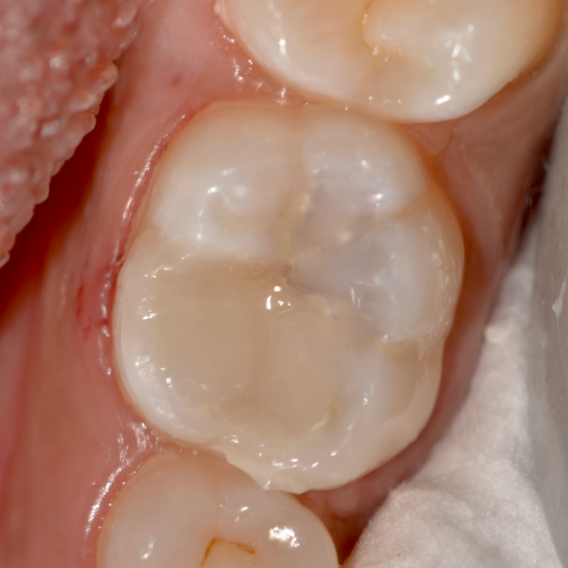

During the follow up period of four months, the restoration showed no unfavorable events. It displayed excellent quality with no marginal failure. No signs of gingival inflammation or increased plaque accumulation was observed. After four months the restoration showed a satisfactory clinical performance considering patient with high caries index (Fig. 12).

Fig 12. 4 months follow up